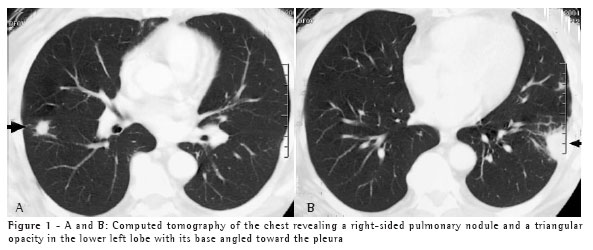

A 67-year-old white male, resident of the city of Blumenau, in the state of Santa Catarina, and a sales representative, presented with dyspnea, asthenia, chest pain, and sweats ten days after having cleaned his attic, where there are water tanks. He was in contact with bat guano for a limited period of time when the area was being swept. The presence of pulmonary nodules on the chest X-ray and tomography of the chest (Figures 1A and 1B), together with the absence of expectoration, justified the performance of a biopsy to evaluate the pulmonary nodule.

Epidemiological history can raise diagnostic suspicion. Knowledge of clinical syndromes, together with clinical suspicion, can avoid the use of empirical treatment. Radiological findings, negative test results, and the high frequency of tuberculosis in Brazil were the motivations for prescribing tuberculosis treatment for both patients. Immunodiffusion test results, although negative for these two patients, have high sensitivity and are positive in approximately 75% of cases.(6) Length of exposure determines disease severity. This explains the fact that the second patient, who was the one who swept the area, presented a more severe form of the disease, with diffuse pulmonary alterations on the chest X-ray, and required hospitalization. However, a short exposure time results in focal pulmonary lesions, as in Case 1.